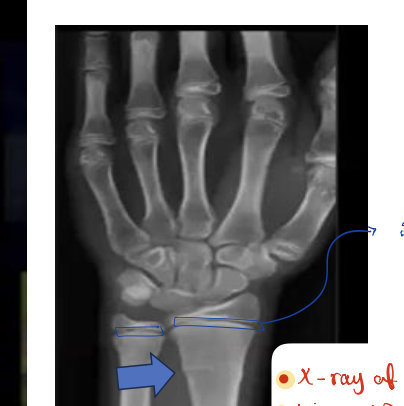

Identify the structures ? name of the bone ? View?

— Antero-Posterior

X-ray of forearm

Carpal bones

Ulna

Radius

Humerus